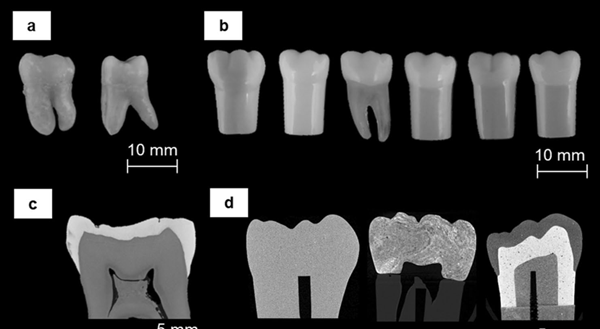

本研究的目的是用模仿天然牙齒的形態(tài)和機械反應(yīng)的材料來3D打印假牙。研究人員使用了X射線顯微層析技術(shù)(XMT)對天然牙齒進行高分辨率成像,以準確繪制樣品的幾何形狀。選擇XMT作為成像技術(shù),是因為它的非破壞性和在結(jié)構(gòu)間輕松分割數(shù)據(jù)的能力,成像數(shù)據(jù)可以被處理并轉(zhuǎn)換為適合3D打印的格式。XMT可以全面描述牙齒的形態(tài),并產(chǎn)生了高對比度的圖像,突出了牙齒之間的結(jié)構(gòu)差異。高對比度掃描清楚地顯示了高礦化的牙釉質(zhì)和低礦化的牙本質(zhì)之間的區(qū)別(在圖像中顯示為明亮的區(qū)域)。一顆商業(yè)類型牙(Frasaco)無高亮區(qū)域,表明釉質(zhì)和牙本質(zhì)都使用了一種材料,或者兩種材料具有相同的X射線不透明度。其余的類型牙都是通過使用不同的材料來區(qū)分釉質(zhì)和牙本質(zhì),導(dǎo)致的XMT圖像有不同的對比。圖f顯示了3D打印材料的重建的XMT圖像。所有的圖像都顯示了幾何形狀和尺寸的統(tǒng)一性,由于額外的填充物顆粒,灰色程度不同。重建的XMT圖像顯示了填充物顆粒(25wt.%)在3D打印結(jié)構(gòu)中的分布。